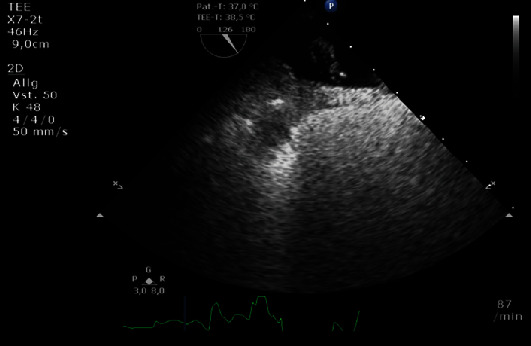

我们为您介绍一例可能因卵圆孔栓塞(PFO)引起的短暂性缺血性发作(TIA)患者。她的病史包括二度心脏传导阻滞 Mobitz II,表现为反复晕厥,曾接受双腔起搏器治疗。在 PFO 介入封堵术中,我们注意到心房起搏器导线被夹在右侧封堵器圆盘和房间隔之间。我们使用一个 24 毫米大小的球囊成功地将导联移至一侧,随后将右侧封堵器盘开发到正确位置。总之,使用尺寸调整球囊可以防止起搏器导联夹在 PFO 闭塞盘和房间隔之间。

We present a case of a patient with a transient ischaemic attack (TIA) likely due to paradoxical embolism through a patent foramen ovale (PFO). Her medical history included 2nd-degree heart block Mobitz II, which manifested with recurrent syncopes and was treated with a dual chamber pacemaker. During the interventional PFO closure procedure, we noted entrapment of the atrial pacemaker lead between the right-sided occluder disc and the interatrial septum. We were able to successfully move the lead aside using a 24 mm sizing balloon and subsequently developed the right-sided occluder disc in the correct position. In conclusion, pacemaker-lead entrapment between a PFO occluder disc and the interatrial septum can be prevented using a sizing balloon.